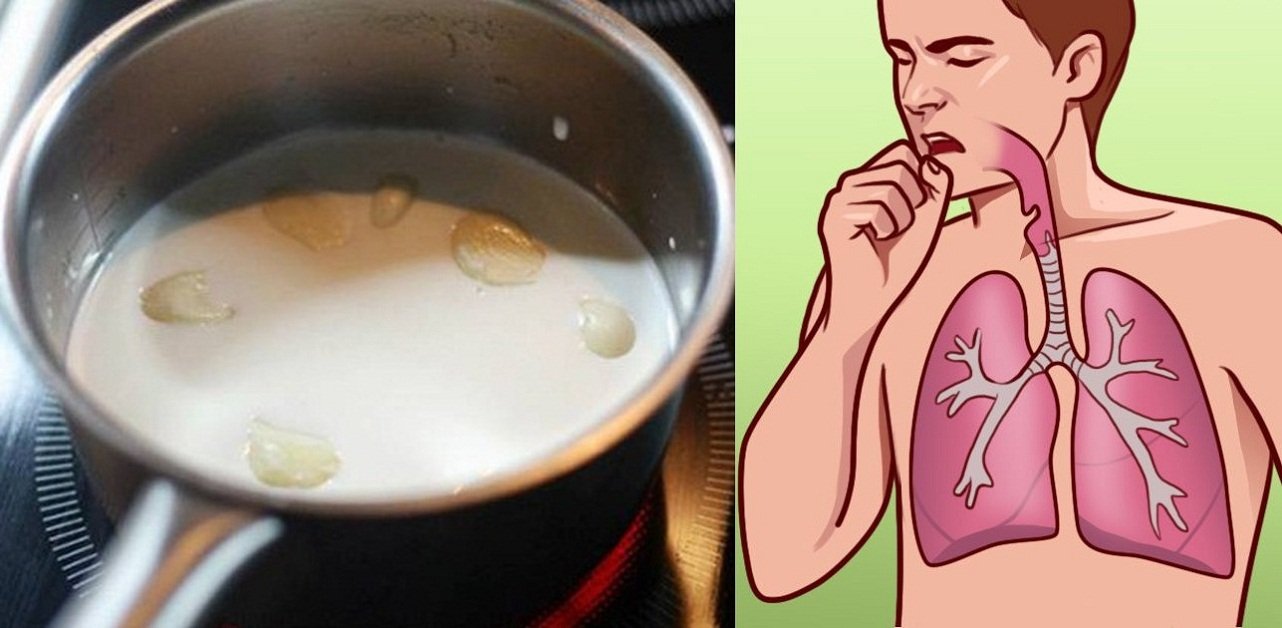

Еда для Легких и Бронхов - Полезные Рецепты